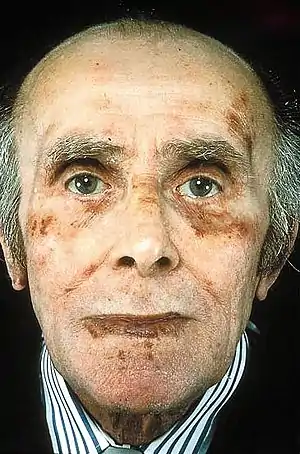

| Classic facial features of AL amyloidosis with bleeding under the skin (bruising) around the eyes[1] | |

A rare development is amyloid purpura, a susceptibility to bleeding with bruising around the eyes, termed "raccoon-eyes", caused by amyloid deposition in the blood vessels and reduced activity of thrombin and factor X, two clotting proteins that lose their function after binding with amyloid.[6]